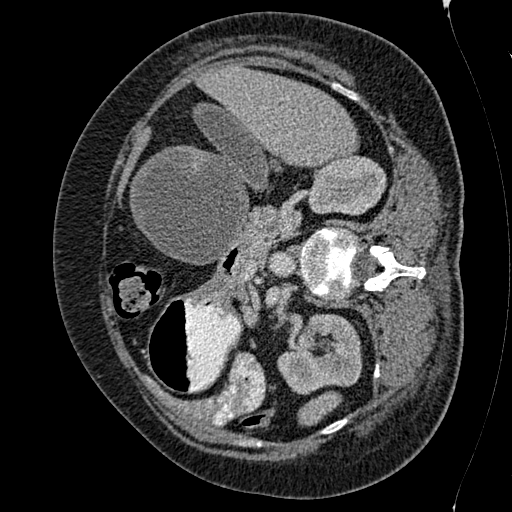

This challenge includes liver segmentation and liver tumor segmentation. The dataset consists of 131 training datasets and 70 testing datasets, all of which are 3D abdominal CT scan images that contain liver. Label maps (annotations) are provided for the training data, but not for the testing data. Participants are required to train their model on the training data, then use the well-trained model to make predictions for the testing data. The prediction can be submitted back to the orgnizer for blind evaluation. An example 3D CT data visualized in different directions is shown in Figure 5.

Refer to caption

Figure 5: Different positions of an example 3D CT data. Upper left: oblique coronal position. Upper right: add annotation (label) to the upper left image, where yellow area is the liver, green areas are the tumors on the liver. Lower left: sagittalia position; lower right: oblique-axial position.